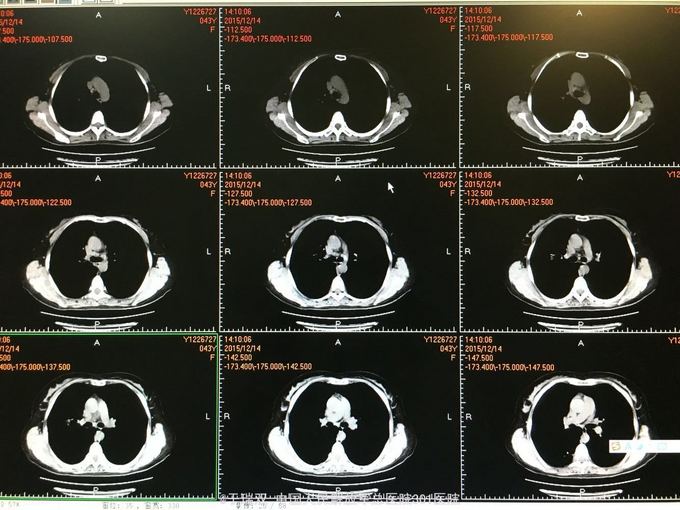

患者中年女女性,2014年10月无明显诱因出现咳嗽咳黄白痰,伴有喘息,自行药物治疗无好转。2014年11月下旬就诊于北京某医院诊断为“变应性支气管肺曲霉病、真菌性肺炎”先后给予伊曲康唑静滴及口服伏立康唑抗真菌、平喘等治疗后症状好转。复查CT炎症也吸收好转,于2015年3月停用以上药物。2015年11月患者再次出现上述症状,胸部CT见右肺班片状实变影,就诊于我院给予左氧氟沙星、西替利秦及化痰止咳治疗后略有好转,遂住院。2015年11月5日CT(图1、2),2015年12月14CT(图3、4、5、6)

该患者最后诊断考虑哪种?患者反复曲霉感染原因是什么? 如何规范治疗,疗程?停药的指征? 患者家中无宠物饲养史,居住环境有潮湿情况,但家中其他人无此种病例。 肺曲霉菌病是真菌感染性疾病中的一种特殊类型,病死率可达30~90%,该病可分为曲霉菌球、变态反应性支气管肺曲霉菌病及侵袭性肺曲霉菌病3种主要类型。